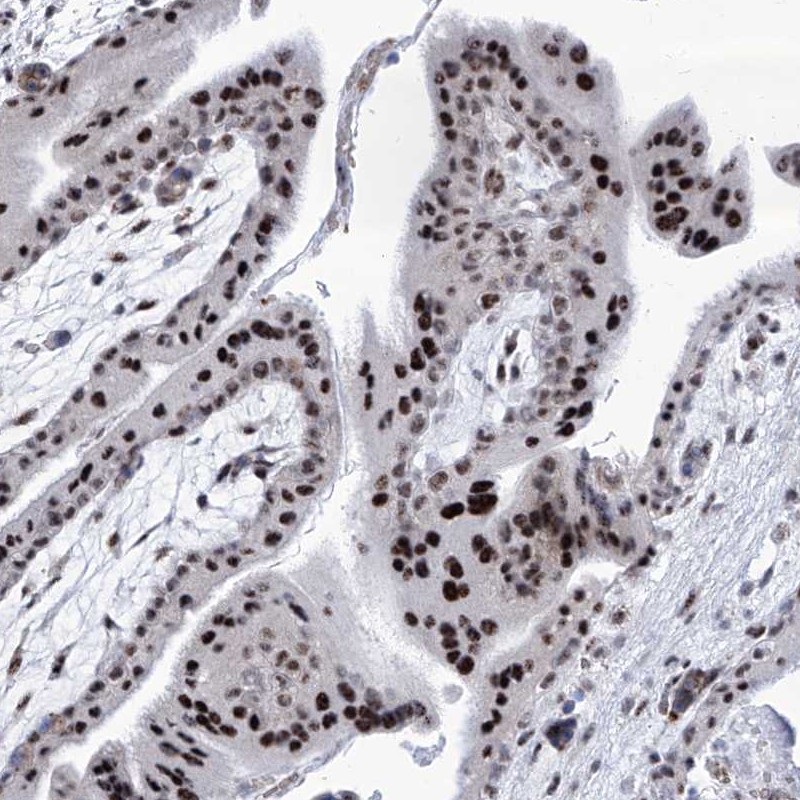

Immunohistochemical staining of human placenta shows strong nuclear positivity in trophoblastic cells.